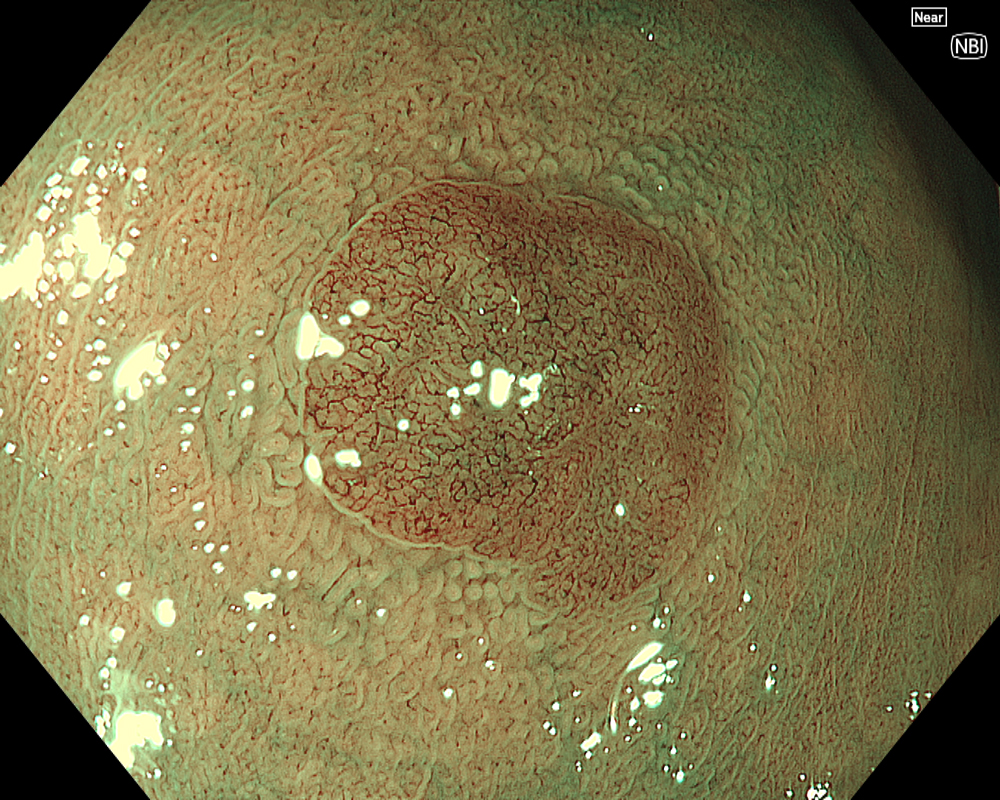

Figure 3: NBI image in near-focus mode under water immersion. Water immersion eliminates halation and provides clear images, while also enhancing magnification for more detailed observation.

In addition to eliminating halation, underwater observation has a magnification effect. When combined with the Near focus mode, it allows for even clearer magnified images. For determining the indication for CSP, the JNET (Japan NBI Expert Team) classification is used, which evaluates the surface Vessel pattern and Surface pattern using NBI + Near focus magnified observation. If the lesion is classified as Type 2A (characterized by a regular caliber and regular distribution (meshed/spiral pattern) in the Vessel pattern, and a regular pattern (tubular/branched/papillary) in the Surface pattern), it is highly likely to be a lowgrade intramucosal neoplasia, and CSP can be indicated if the size is less than 10 mm. If the lesion is classified as Type 2B (characterized by variable caliber and irregular distribution in the Vessel pattern, and an irregular or obscure pattern in the Surface pattern), there is a higher possibility of high-grade intramucosal neoplasia or deeper invasion. Indiscriminately performing CSP based solely on small size should be avoided in these cases.